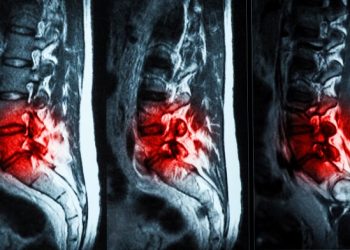

Читать далееХроническими болями в пояснице по причине изношенности межпозвоночных дисков страдают миллионы людей. Основная функция дисков — амортизация позвонков. Однако со...